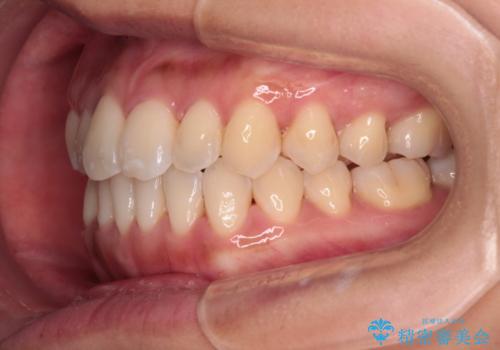

上顎前歯が捻れて前方に飛び出しており、下顎前歯もそれに沿うようにデコボコとなっていました。

IPR(歯と歯の間を削る処置)によりスペースを獲得して上下顎前歯のデコボコを改善し、飛び出している前歯が引っ込むように設定し、インビザラインにて矯正治療を行うこととしました。

装着時間を守ってくださったので、予定通りの期間で終えることができました。インビザライン特有の、奥歯の咬み合わせの問題もなく、しっかりと歯列を改善することができました。